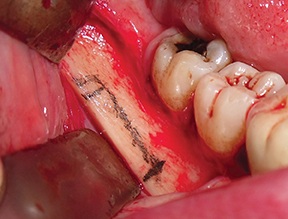

To make osteotomy execution easier, it is advisable to mark them directly on the cortical bone with a pencil (Fig. 6).

Using an ultrasonic device with dedicated T-Black inserts (ES007T and ES009NT), a cortico-cancellous bone block was outlined and osteotomized (Figs. 7–8).

To facilitate block mobilization, it is important that the osteotomy lines partially overlap at the corners (Fig. 9).

Fig. 6: Osteotomies marked on the cortical bone with a pencil

Fig. 7: Osteotomy performed with an ultrasonic tip (ES009NT)

Fig. 8: Osteotomy performed with an ultrasonic tip (ES007T)

Fig. 9: Overlapping osteotomy lines at the corners to facilitate block mobilization